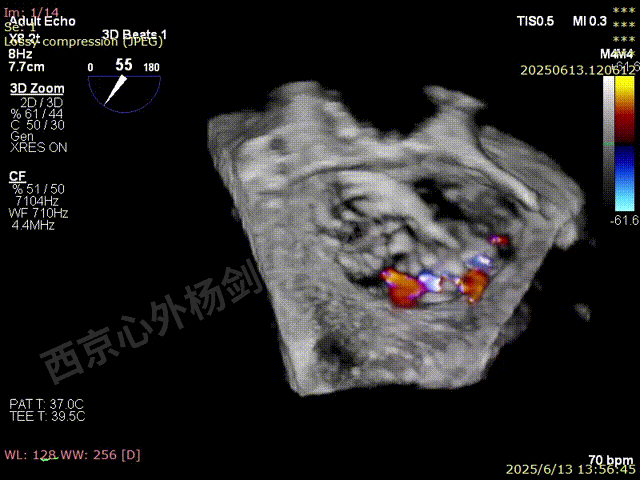

TEER术前超声评估

图片

二尖瓣后叶栓系严重,前叶相对错位,反流束沿2区分布广泛,2偏3区处存在反流。

反流宽度至少23mm,因影像调整困难,考虑实际反流更宽。